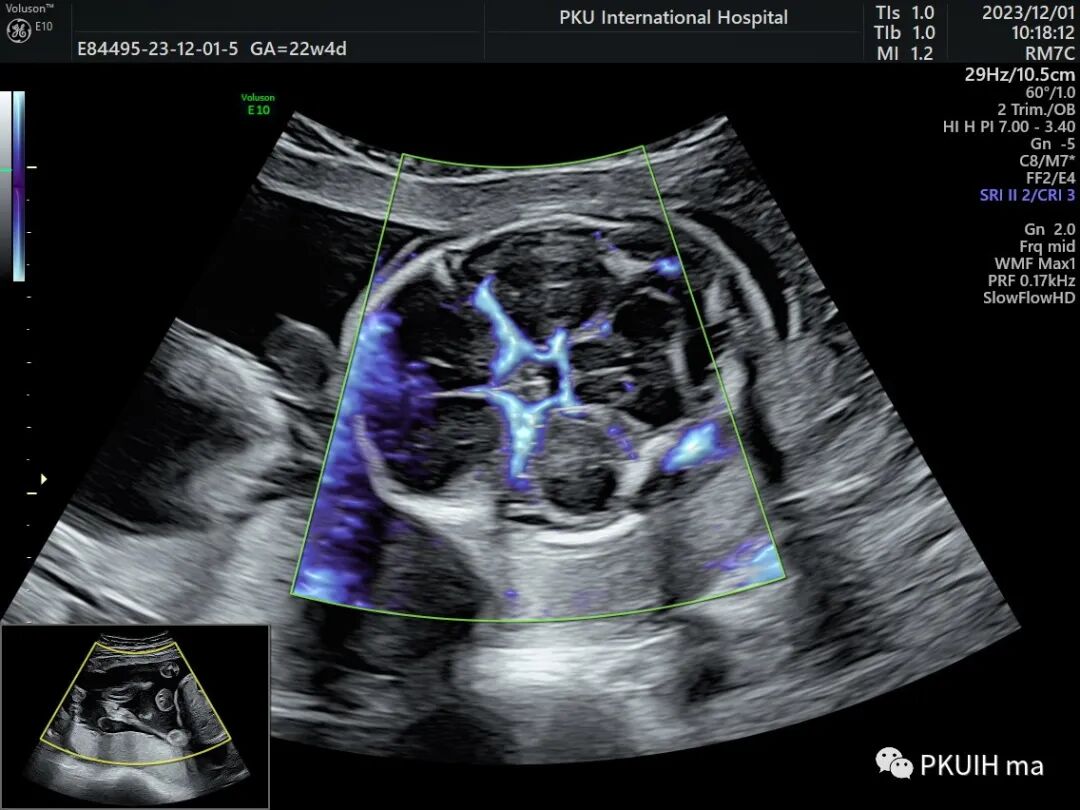

GE的SlowFlow功能还是有作用的。看看下面这几张,第一第二张图用CD和HD都不能完美的显示胎儿大脑Willis环,采用SlowFlow功能能够显示完整的颅底动脉环

通过这个血流成像前交通后交通都能完美显示